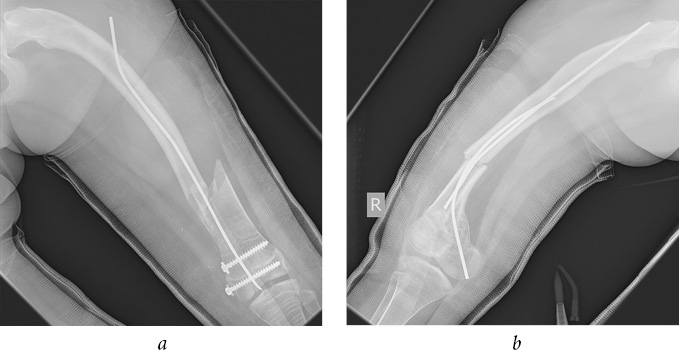

According to the radiographs performed in a primary care facility (of poor quality, in one projection), a closed, comminuted intra-articular fracture of the distal metaepiphysis of left femur (Salter-Harris IV) was diagnosed with a transition to the shaft with the displacement of fragments (Fig. 2); in addition, a closed fracture of the right femoral bone in the lower third of the shaft with mild displacement of fragments was observed (Fig. 3). TEN in the intramedullary canal of right femur prevented a severe displacement of the fragments. As a result of the fracture, TEN was deformed.

Fig. 2. Intraoperative radiographs of the left femur: a — frontal view; b — lateral view

Fig. 3. Intraoperative radiographs of the right femur: a — frontal view; b — lateral view